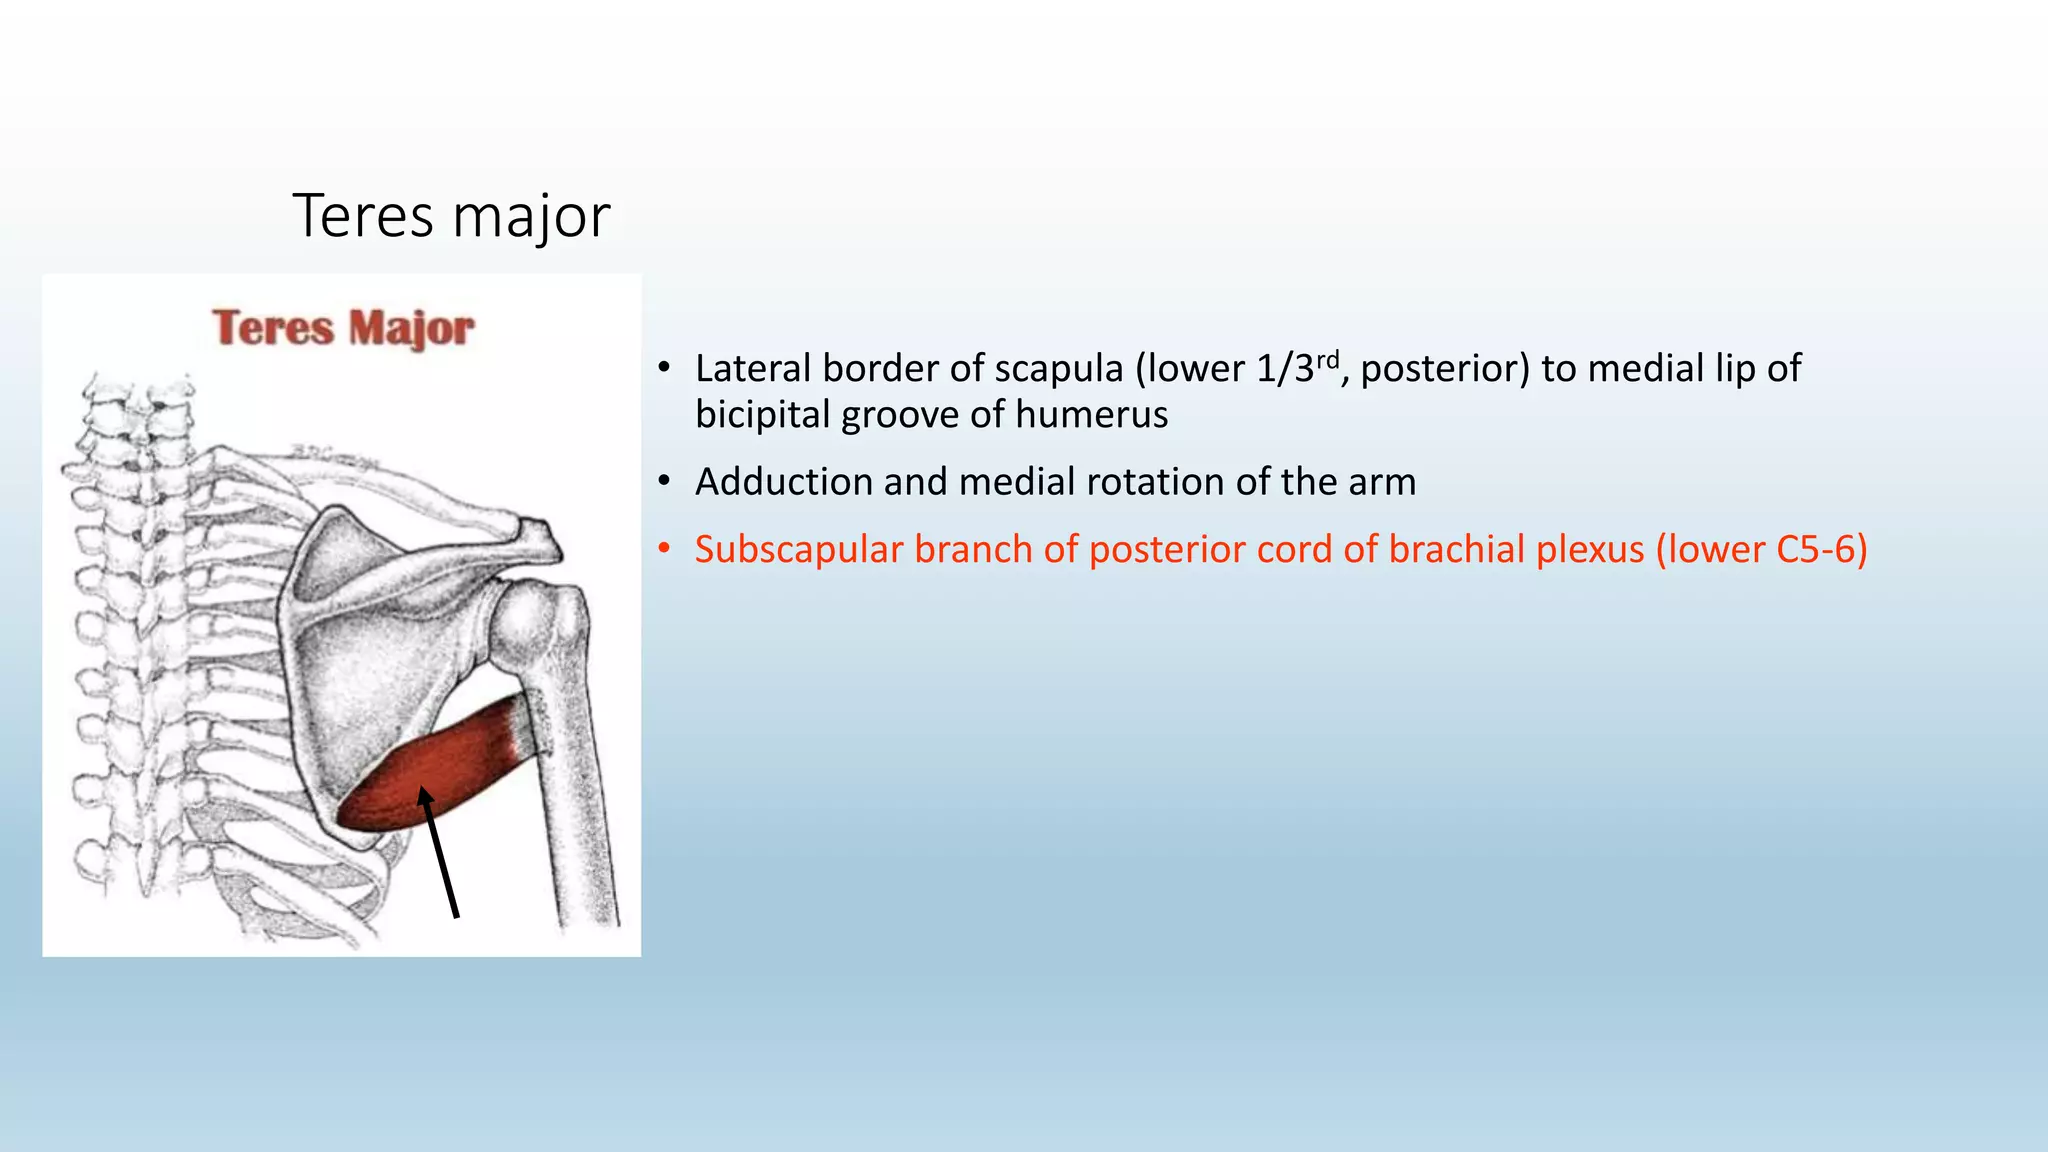

The document summarizes an anatomy revision session on the upper limb. It discusses various muscles of the upper limb including their origins, insertions, innervations and functions. Key muscles covered include the pectoralis major and minor, serratus anterior, deltoid, biceps brachii, brachialis, coracobrachialis, and triceps. It also discusses the rotator cuff muscles and muscles of the forearm including flexor carpi ulnaris and radialis. The session aims to help students identify upper limb muscles and understand their relations to nerves.